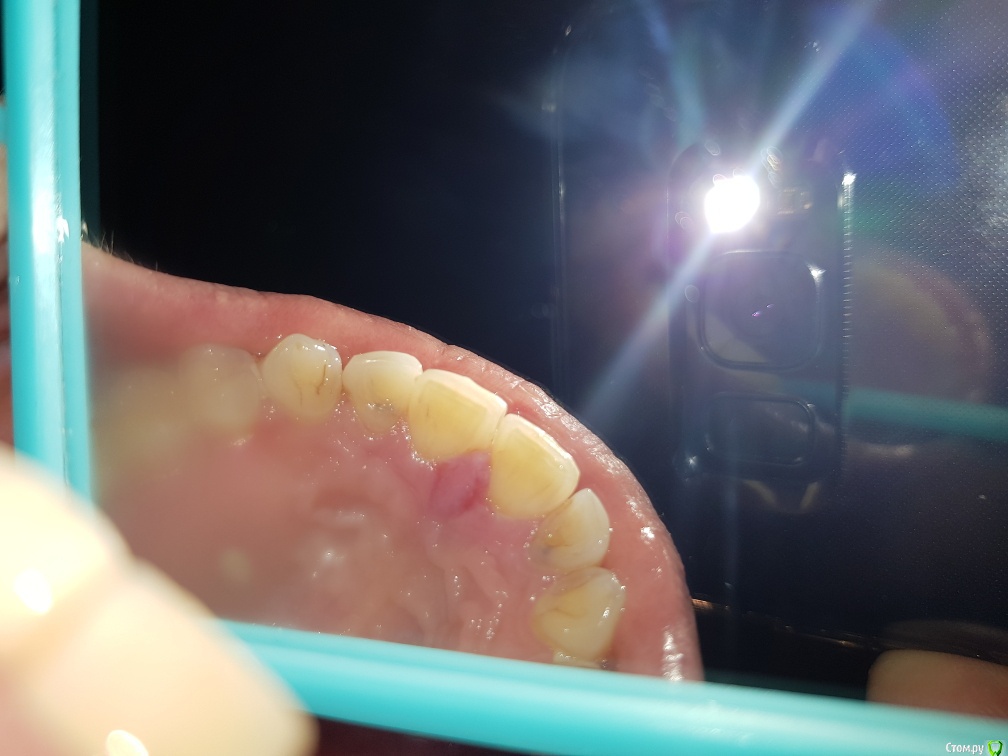

Здравствуйте. 10 мая 2019 года мне сделали эстетическую реставрацию диастемы между передними зубами. Через 2 дня воспалился резцовый сосочек. Лечили Метрогил Дента, Холисал, полоскание солью, пародонтолог прижигал сосочек 3 раза. Ничего не помогло. Сделали КТ- все в норме, была на консультации у хирурга - ничего не видят, проблему не могут найти. Два раза шлифовали пломбу. Помогите установить причину. КТ по ссылке на гугл диске

post-58052-0-01420300-1561453155_thumb.jpg